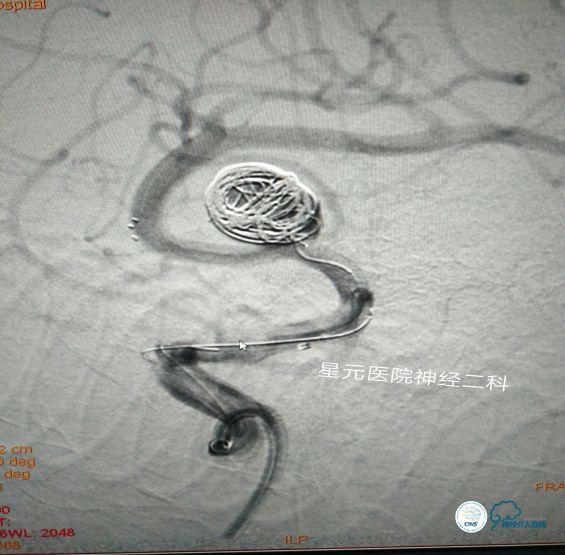

方案三:支架辅助双导管弹簧圈栓塞技术

➤回撤微导管A,支架保持不动,通过微导管B在瘤体底部眶额支开口方向小范围内进行弹簧圈的半释放,将眶额支开口处用弹簧圈充填!

➤通过微导丝将微导管A输送至瘤体腔内,然后通过微导管A进行对瘤顶部其余空间弹簧圈的缓慢致密栓塞。

➤将微导管B内的弹簧圈缓慢退出,造影证实,眶额支开口良好,血流通畅,将回收的弹簧圈通过微导管A再次进行致密充填!

➤栓塞完毕后,缓慢回撤微导管A,通过Naviven造影,了解充填情况。最后熔断释放支架。术毕,患者安返病房!